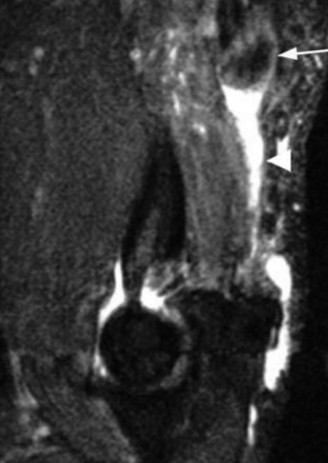

You send the patient for an MRI, which is shown in Figure 2–66.

Figure 2–66

The correct answer is (C). The patient’s clinical examination findings of isolated

weakness in external rotation and atrophy of the infraspinatus muscle point to suprascapular nerve entrapment at a location past the exit point for the branch to the supraspinatus muscle. Also, MRI reveals a posterior labral tear with a paralabral cyst that is compressing the suprascapular nerve at the spinoglenoid notch. Choice A, while fitting with the patient’s clinical examination, does not fit with the MRI showing paralabral cyst. Choices B and D are incorrect because entrapment of the suprascapular nerve at the suprascapular notch by scapular body fracture or by the transverse scapular ligament (more common) would lead to weakness/atrophy in both supraspinatus and infraspinatus muscles as the suprascapular notch is proximal to the nerve branch point to the supraspinatus muscle.

What is the most appropriate treatment at this time?

- Arthroscopic decompression of the paralabral cyst and labral repair

The correct answer is (B). The patient has a clear etiology for his suprascapular nerve decompression in the paralabral cyst with symptoms that have lasted for 6 months resulting in atrophy of the infraspinatus muscle. Given that he is a college-level athlete and likely wants to improve his athletic performance, surgical decompression of the suprascapular nerve at the spinoglenoid notch is indicated at this time, which can best be accomplished arthroscopically along with labral repair. Choice D is incorrect as the patient does not require decompression of the nerve at the suprascapular notch, since he shows no sign of weakness/atrophy of the supraspinatus muscle. Choice A would be appropriate for a patient with symptoms of suprascapular nerve compression for less than 6 months of duration, without atrophy, and without any compressive mass on MRI. Choice C could aid in establishing a baseline for treatment and could localize nerve entrapment sites in a patient whom the location of suprascapular nerve entrapment was unclear but is not the most appropriate treatment for this particular patient. Objectives: Did you learn...? Recognize the clinical presentation of suprascapular neuropathy?